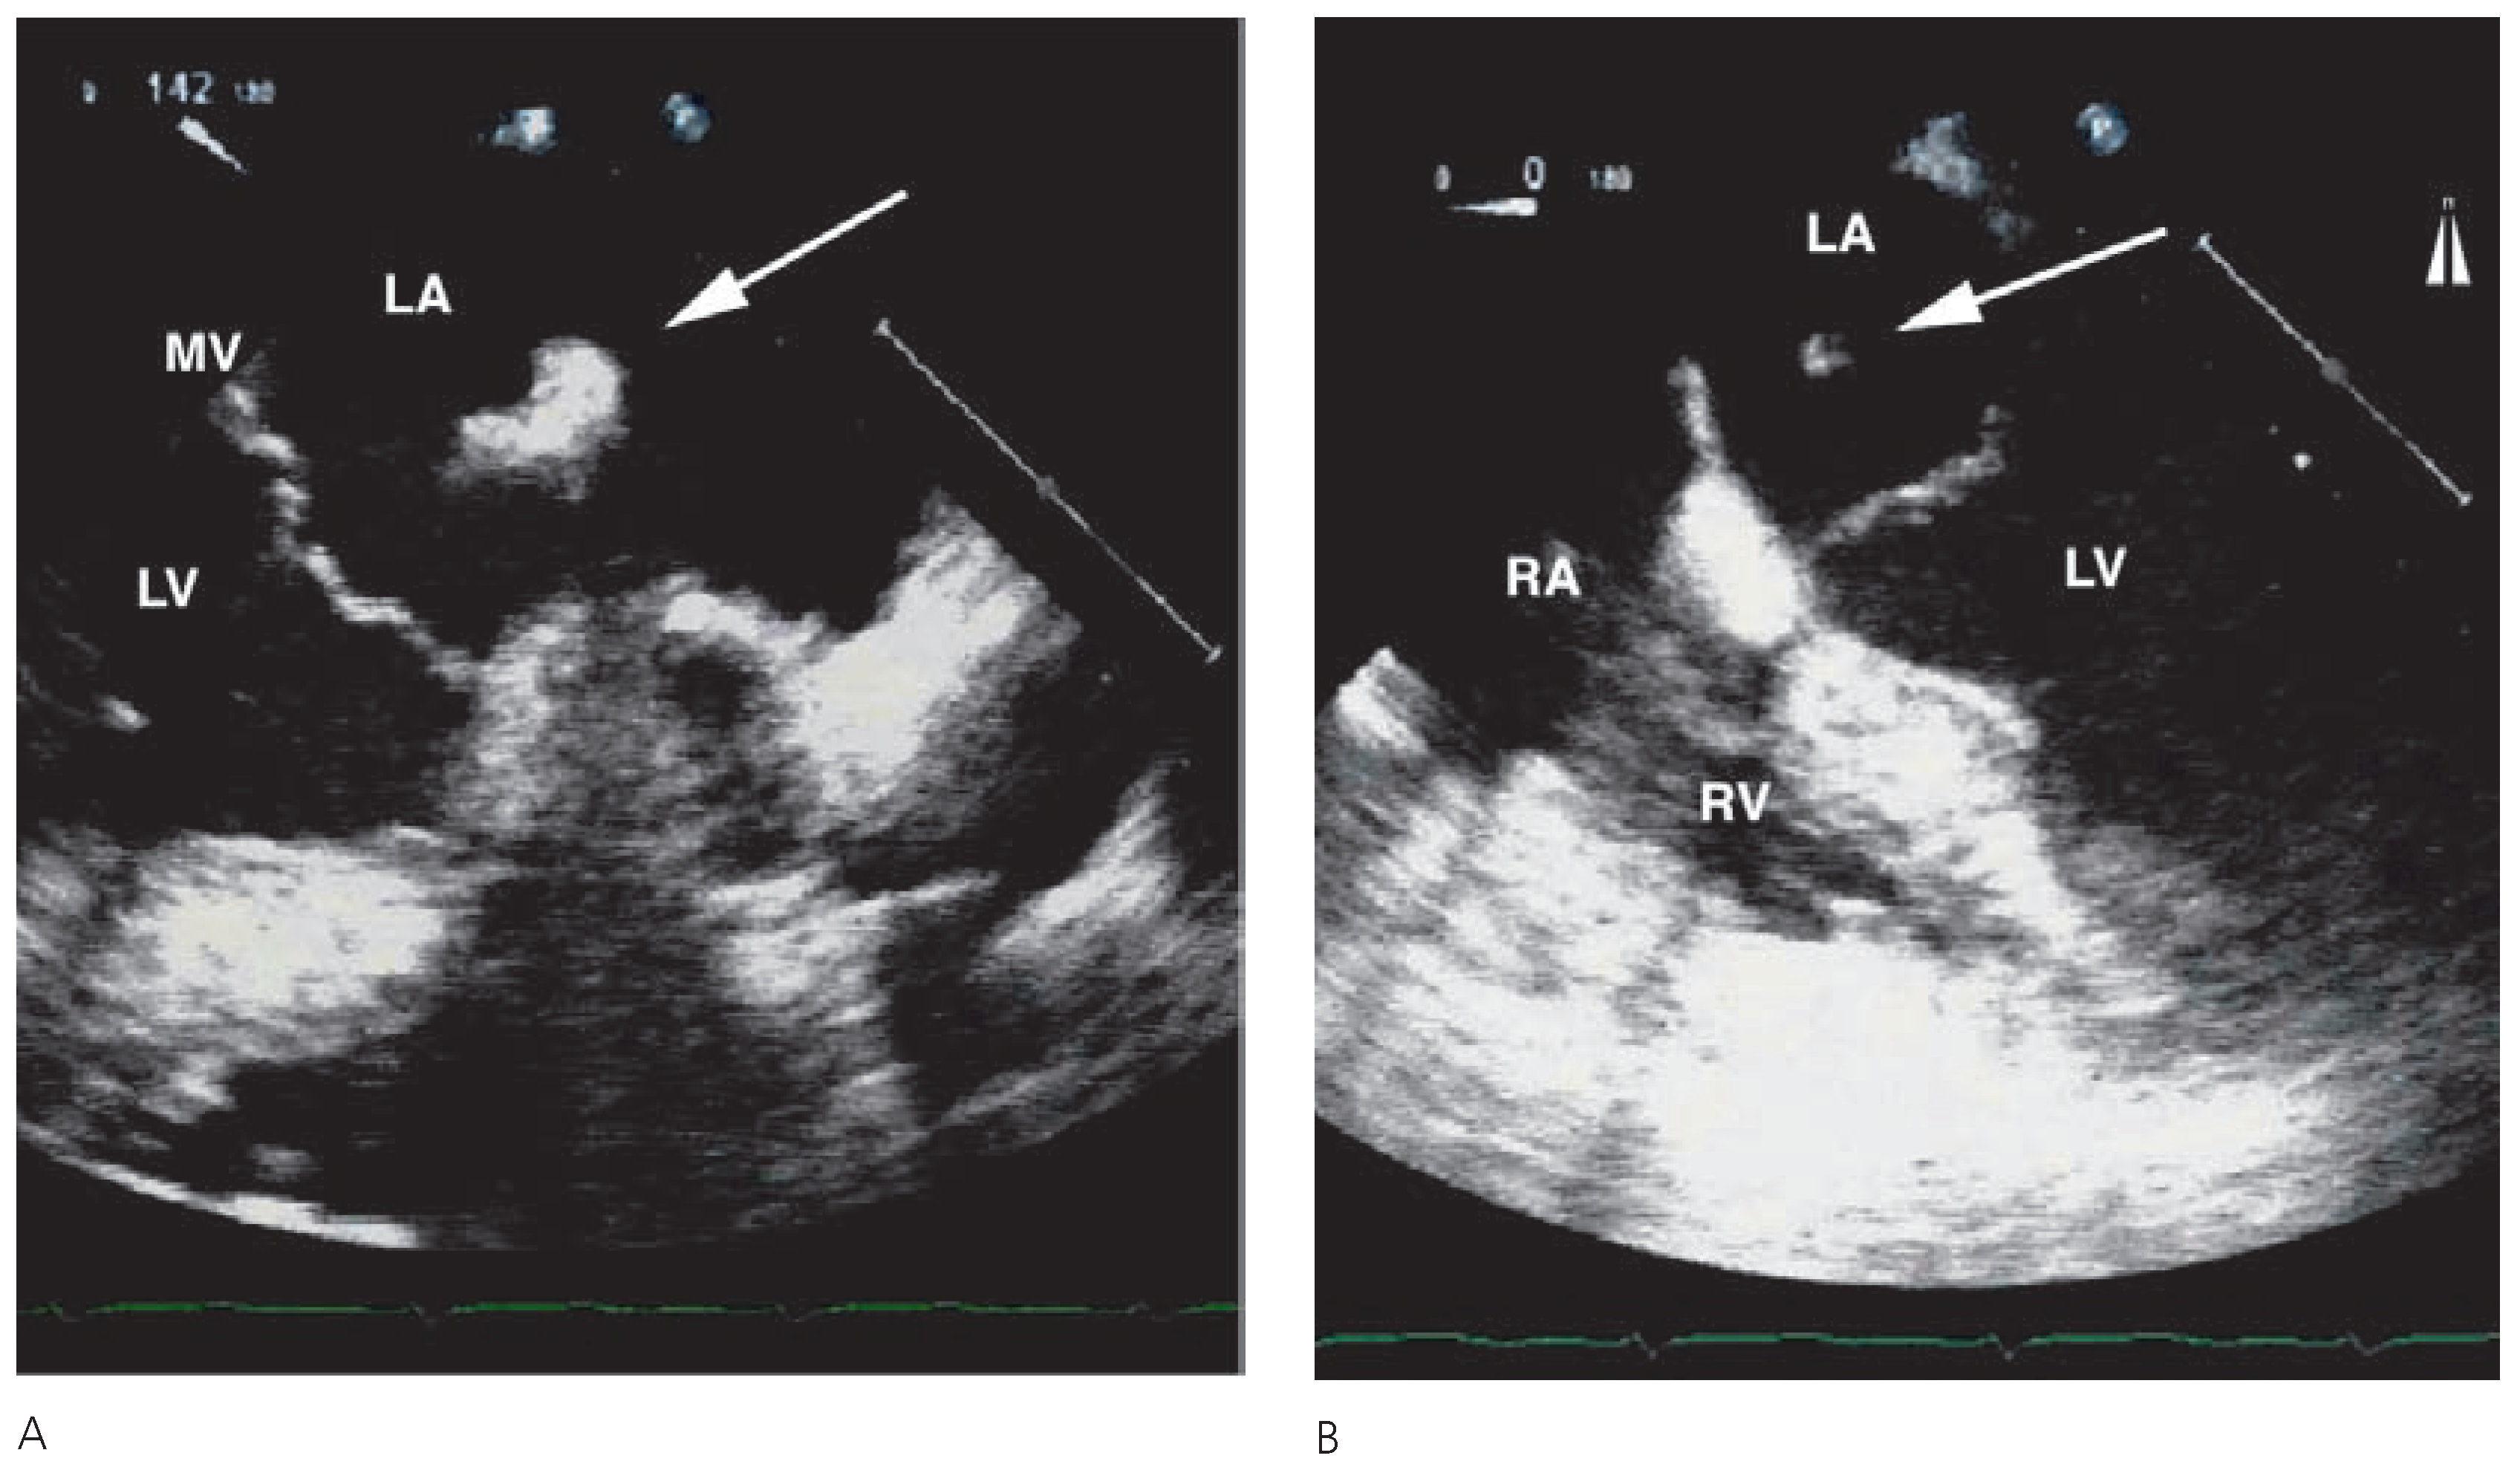

Mysterious Floating Structure in the Left Atrium After Coronary Artery Bypass Grafting